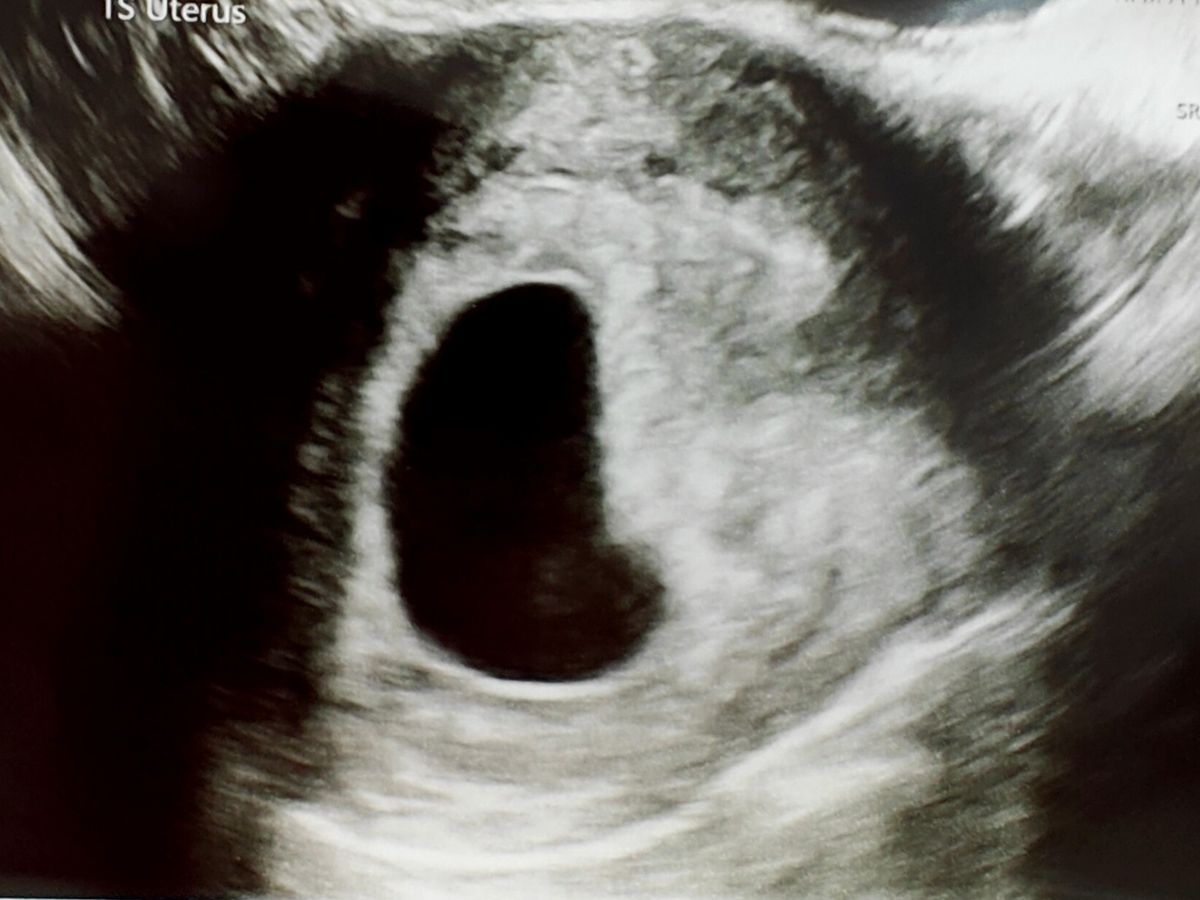

However, Kerry experienced a sudden and unexpected bleed at work one day and we rushed to the hospital. As the bleeding increased, we consigned ourselves to the worst and, after several hours and a review, were sent away to be scanned by a specialist the next day. the 12 hours between A & E discharge and that scan were what I thought would be the worst experience possible. Neither of us slept and simply tried to control our emotions for the sake of the other. The scan came and, against all odds, the heartbeat was still there and we still had a chance at success. A small haematoma (pocket of blood) was found to be the source of the bleeding and something that is fairly common in women undergoing IVF related treatments. Nevertheless, a follow up scan was arranged for 9 days time at the local community unit to ensure everything was progressing nicely. The follow up scan, once again, showed typically development and little change in the haematoma, finally giving us a chance to start relaxing and giving in to baby shopping and endless blissful planning.

As these investigations were conducted through the NHS, we were still awaiting our discharge scan with our IVF Fertility Clinic near Nottingham. We headed up to Nottingham on Friday feeling safe and confident, giving the glowing scan experienced just days before. After a 30 minute wait, the scan was conducted and, from the haze of memory, it was less than two minutes later we had confirmation that the heartbeat was no more and we'd lost our chance. There was no bleeding and no unusual pain. There was no warning. The last 48 hours have been filled more despair than I have ever known. Both Kerry and myself feel that the entire future has been torn away from us and there is nothing that will take away from that. We find ourselves looking for a cause and for answers that will we likely never get, combined with the haunting reality of seeing a billion moments of a life that will never be. There are so many plans for a future that now won't happen and it is still tearing us apart.